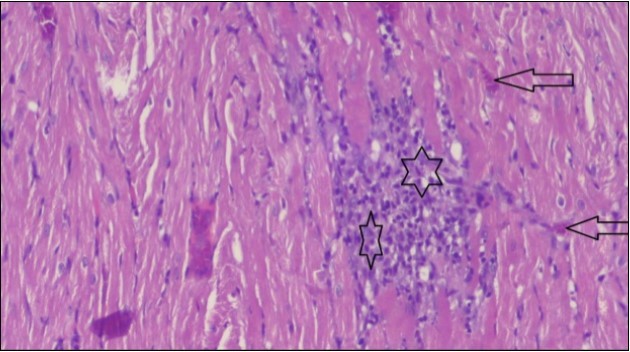

An important organ that is affected directly by the obesity which is the heart: The heart is the main important organ in circulatory system, the heart wall has three basic layers; the tunica intima of the heart is called endocardium, the tunica media of the heart is called the myocardium, the tunica adventitia of the heart the epicardium. The histological examination of the hearts of control rats feeding standard diet showing normal cardiac tissue with elongated, unbranched multinucleated muscle fibers (arrow), (Figure 1). The rats are feeding (HFD) for 2 weeks (obese rats) showing large number of inflammatory cells (star), degeneration muscles fiber ,circle and congested Blood vessels (arrow) (Figure 2). By comparison hearts of rats are treated by fennel after obesity and control rats observed show improved cardiac tissue with less infiltration (star) and well organized elongated muscle fibers with peripheral nuclei (arrow) (Figure 3). While examination of rats heart that treated by ator after obesity appears show less improved cardiac tissue with few inflammatory cells between disorganized muscle fiber (star), (Figure 4). While combined hearts of rats are treated by fennel and ator after obesity and control mice are showing nearly cardiac tissue with well-organized muscles fibers (arrow), (Figure 5).

Figure 2.Photomicrograph of heart section of an obese rat showing large number of inflammatory cells (star), degeneration muscles fiber, circle and congested Blood vessels (arrow), (H&E) (400X).

Figure 4.Photomicrograph of heart section of treated rat with Ator drug showing less improved cardiac tissue with few inflammatory cells between disorganized muscle fiber (star), (H&E) (400X).